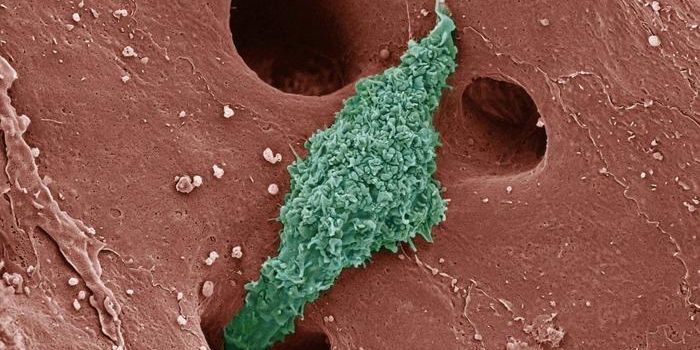

AUG 26, 2024Clinical & Molecular DXA colorized scanning electron micrograph depicts a Kupffer cell. / Credit: Thomas Deerinck, National Center for Microsco ...